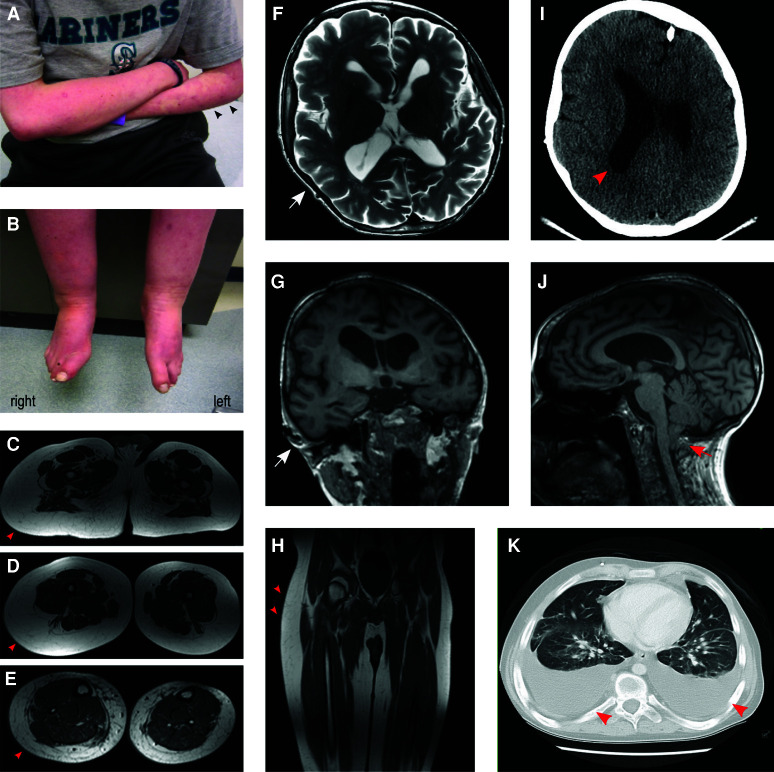

巨脑-毛细血管畸形(MCAP)综合征是一种由PIK3CA嵌合性功能获得变异引起的过度生长障碍,其特征为巨脑畸形或半巨脑畸形、血管畸形、躯体过度生长等特征。癫痫通常与MCAP相关,并且一部分个体有皮质畸形,需要切除性癫痫手术。与其他花叶病一样,建立分子诊断主要是通过筛查病变组织(如脑或皮肤)来实现的,外周组织(如血液)的诊断率较低。因此,对于病变组织稀缺或无法获得或不适合癫痫手术的MCAP患者,建立分子诊断可能具有挑战性。在这里,我们报告了脑脊液(CSF)来源的cfDNA在MCAP综合征个体携带马赛克PIK3CA变异(c.3139C > T, p.His1047Tyr)的分子诊断中的应用。先证者表现为不对称巨脑畸形,无明显脑功能障碍。他没有难治性癫痫,因此不适合进行癫痫手术。然而,他在儿童晚期发展为弥漫性大b细胞淋巴瘤(DLBCL),通过腰椎穿刺获得4份脑脊液样本用于癌症分期,其中1份样本用于cfDNA提取和测序。PIK3CA变异等位基因在CSF无细胞DNA (cfDNA)、皮肤成纤维细胞和外周血中的比例分别为3.08%、37.31%和2.04%。本报告阐述了csf来源的cfDNA在MCAP综合征中的应用。基于cfDNA的微创分子诊断方法不仅有助于准确的遗传诊断,而且随着PI3K-AKT-MTOR通路抑制剂的应用越来越广泛,对难治性癫痫患者具有重要的治疗意义。

The megalencephaly-capillary malformation (MCAP) syndrome is an overgrowth disorder caused by mosaic gain-of-function variants in PIK3CA It is characterized by megalencephaly or hemimegalencephaly, vascular malformations, somatic overgrowth, among other features. Epilepsy is commonly associated with MCAP, and a subset of individuals have cortical malformations requiring resective epilepsy surgery. Like other mosaic disorders, establishing a molecular diagnosis is largely achieved by screening lesional tissues (such as brain or skin), with a low diagnostic yield from peripheral tissues (such as blood). Therefore, in individuals with MCAP in whom lesional tissues are scarce or unavailable or those ineligible for epilepsy surgery, establishing a molecular diagnosis can be challenging. Here we report on the utility of cerebrospinal fluid (CSF)-derived cfDNA for the molecular diagnosis of an individual with MCAP syndrome harboring a mosaic PIK3CA variant (c.3139C > T, p.His1047Tyr). The proband presented with asymmetric megalencephaly without significant dysgyria. He did not have refractory epilepsy and was therefore not a candidate for epilepsy surgery. However, he developed diffuse large B-cell lymphoma (DLBCL) in late childhood, with four CSF samples obtained via lumbar puncture for cancer staging during which one sample was collected for cfDNA extraction and sequencing. PIK3CA variant allele fractions in CSF cell-free DNA (cfDNA), skin fibroblasts, and peripheral blood were 3.08%, 37.31%, and 2.04%, respectively. This report illustrates the utility of CSF-derived cfDNA in MCAP syndrome. Minimally invasive-based molecular diagnostic approaches utilizing cfDNA not only facilitate accurate genetic diagnosis but also have important therapeutic implications for individuals with refractory epilepsy as repurposed PI3K-AKT-MTOR pathway-inhibitors become more widely available.